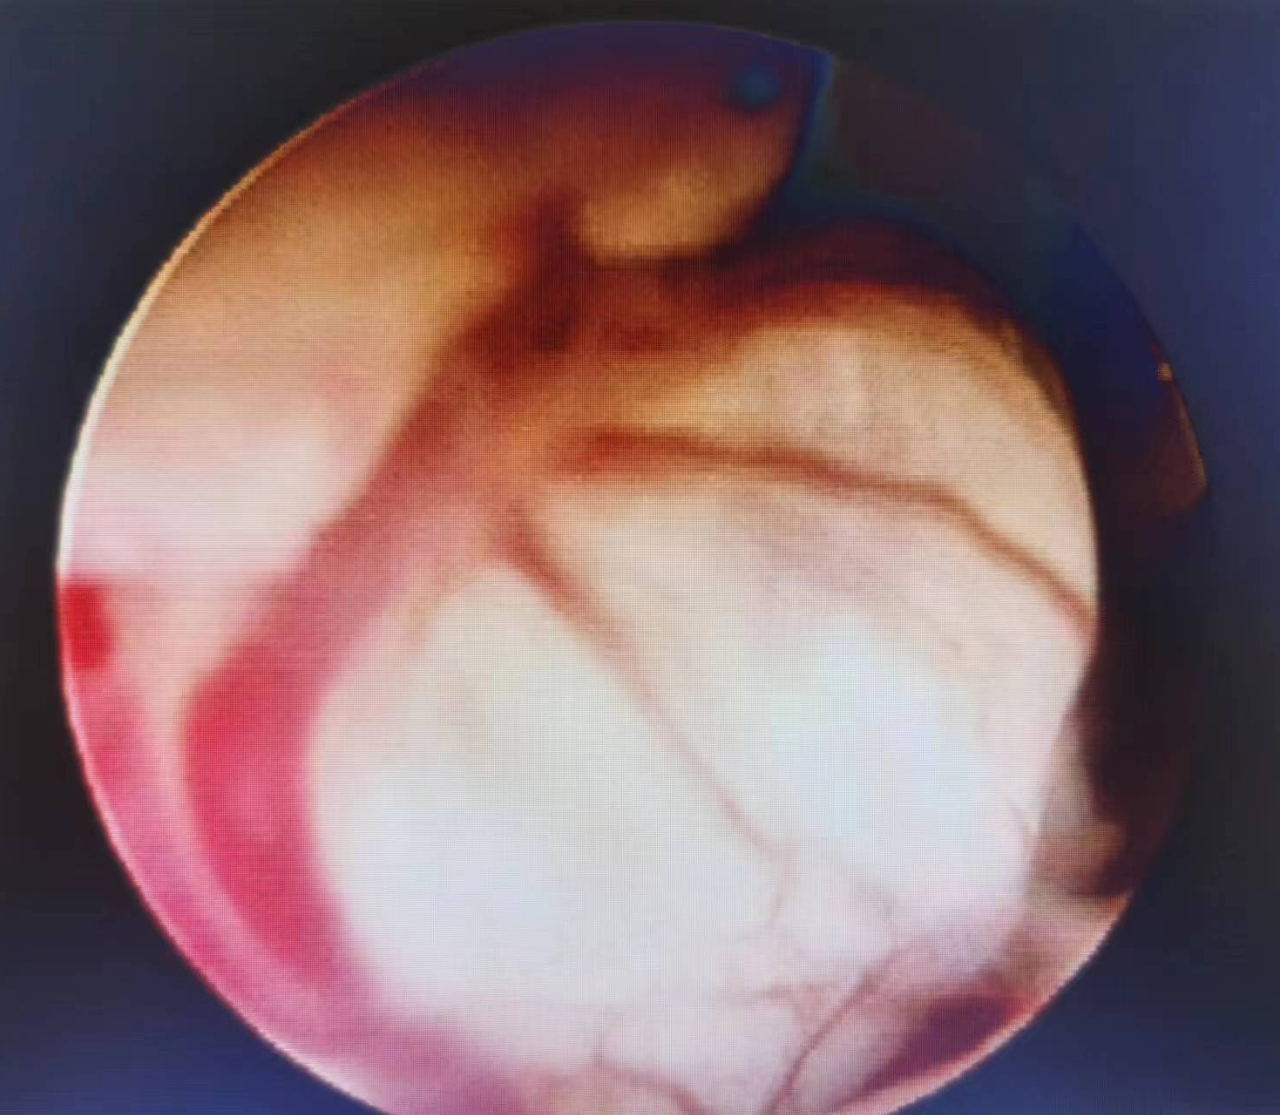

内膜增厚伴增生小血管